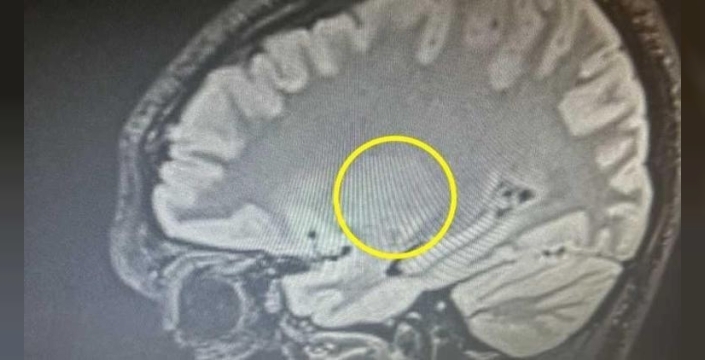

The Sun'ın haberine göre, başlangıçta viral bir enfeksiyon olabileceği düşünülen doktorlar, 29 Kasım'da yapılan BT ve MR taramaları sonucunda Max'in beyninde büyük bir tümör tespit etti. Ameliyat edilemeyecek olan tümörün konumu nedeniyle tedavi şansı bulunmadığı belirtildi. Max'in babası, nöroloji uzmanının tümörün büyük olduğunu ve uzun süredir orada olması gerektiğini söyledi. Tümör, beynin iletişim, konuşma ve hafızadan sorumlu bölgesinde yer alıyor ve biopsi sonuçları kanser türünü belirleyecek. Max'in kısa süreli hafızasında bozulmalar, mide bulantısı, kusma ve sürekli yorgunluk yaşadığı, ayrıca kelimeleri düzgün söylemekte zorluk çektiği, ancak buna rağmen olumlu bir tutum sergilediği ifade edildi. Ailesi, Almanya'da tedavi olabilmesi için GoFundMe üzerinden bağış kampanyası başlattı.